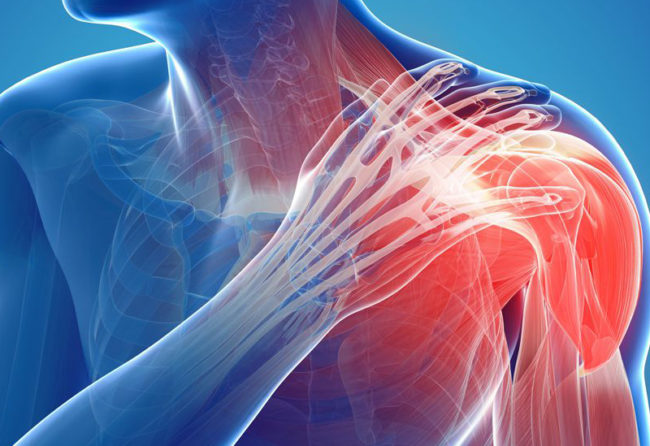

Artritele umarului

Termenul de artrita literar este folosit pentru a descrie o inflamatie intraarticulara, insa se asociaza folosirea lui cu leziunile de cartilaj articular. Astfel distrugerea cartilajului articular in interiorul articulatiei gleno-humerale cauzeaza artrita umarului. Gradul de afectare a cartilajului articular si inflamatia intraarticulara, variaza cu tipul si stadiul artritei. In stadiile avansate, cand nu mai exista…